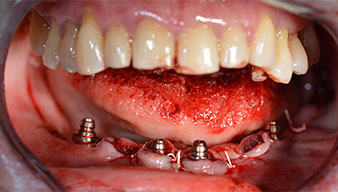

Angled abutments (35°) were screwed in to compensate for the divergence of the distal implants, with the result that the emergence profile of all implants was as perpendicular as possible to the bite plane. This is a prerequisite for occlusal placement of the provisional and subsequently the permanent denture (Fig. 15 and 16).

The impression and bite registration were then performed so that the dental technician could begin producing the provisional restoration immediately. This was then screwed in on the same day (Fig. 17 and 18).